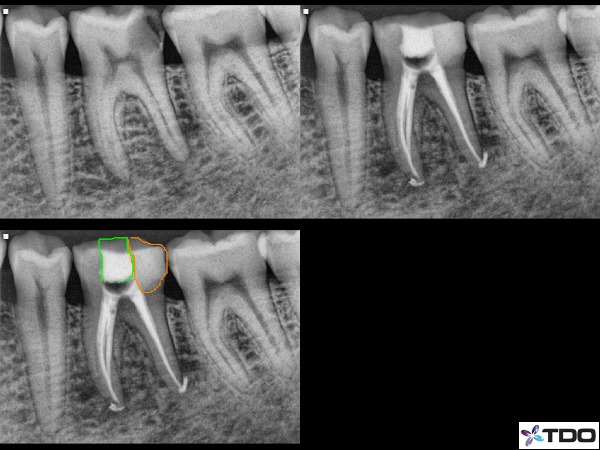

About 6 years ago our office made a significant change in how we deal with proximal decay in association with root canal therapy. That change came in the form of creating protection and stability of the tooth prior to the start of the traditional endodontic therapy with a treatment step called the pre-endodontic build-up. This is an easy concept and thus this blog will certainly be less detailed that others I have written. Simply stated, in cases with significant decay, we rebuild the tooth structure before proceeding with the RCT. Seems reasonable, right? But I feel that the rebuilding of the tooth is too often done once the endodontics is completed. Here is an example: (figure 1)

Fig.1: Common presentation for RCT with interproximal (distal) decay. In this case I first removed the decay entirely and found all canals. I the block out the canal spaces with some form of a barrier (ie. cotton, cavit, etc) and rebuilt the entire surface with composite (orange). Then I reaccessed into the composite to find the barrier material and proceed with RCT. The green is the temporary filling in place through the access point. Tough to see on this x-ray but there were 3 mesial canals and 2 distal canals in this tooth.